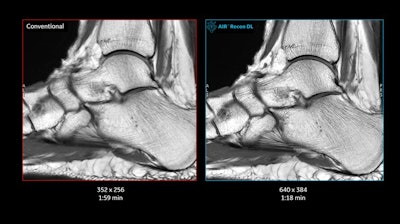

Another major MRI highlight in GE's booth is the company's AIR family of products, which include flexible radiofrequency (RF) coils and software. AIR Recon DL is an image reconstruction algorithm based on deep learning that delivers shorter scan times with improved image quality in a variety of clinical indications, according to the company.

GE is touting the use of AIR Recon DL for managing COVID-19 patients by saving on scanning time that can then be used to disinfect the scanner. Hospital for Special Surgery in New York City, an early user of AIR Recon DL, is reporting a reduction of 30% to 50% in exam times with the technology, with higher signal-to-noise ratio and better resolution. AIR Recon DL is available on all GE 1.5-tesla and 3-tesla scanners and has FDA clearance.